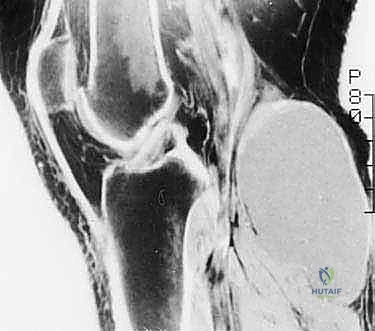

- الرنين المغناطيسي (MRI): هو المعيار الذهبي (Gold Standard) لتقييم الأورام. يوضح بدقة امتداد الورم في النخاع العظمي والأنسجة الرخوة، وعلاقته بالأعصاب والأوعية الدموية.

الحالة الأولى: إنقاذ ركبة رياضي شاب

شاب يبلغ من العمر 19 عاماً عانى من ألم مستمر في الركبة وتورم لم يستجب للمسكنات. بعد الفحص السريري الدقيق وإجراء الرنين المغناطيسي، اشتبه الأستاذ الدكتور محمد هطيف بوجود ورم. تم إجراء خزعة إبرة أساسية دقيقة جداً. أظهرت النتائج وجود "ساركوما عظمية" في مراحلها الأولى. بفضل الخزعة الدقيقة التي لم تلوث الأنسجة المحيطة، تمكن الدكتور هطيف لاحقاً من استئصال الورم بالكامل وتركيب مفصل صناعي خاص بالأورام، مما أنقذ ساق الشاب من البتر ومكنه من العودة للمشي بشكل طبيعي.